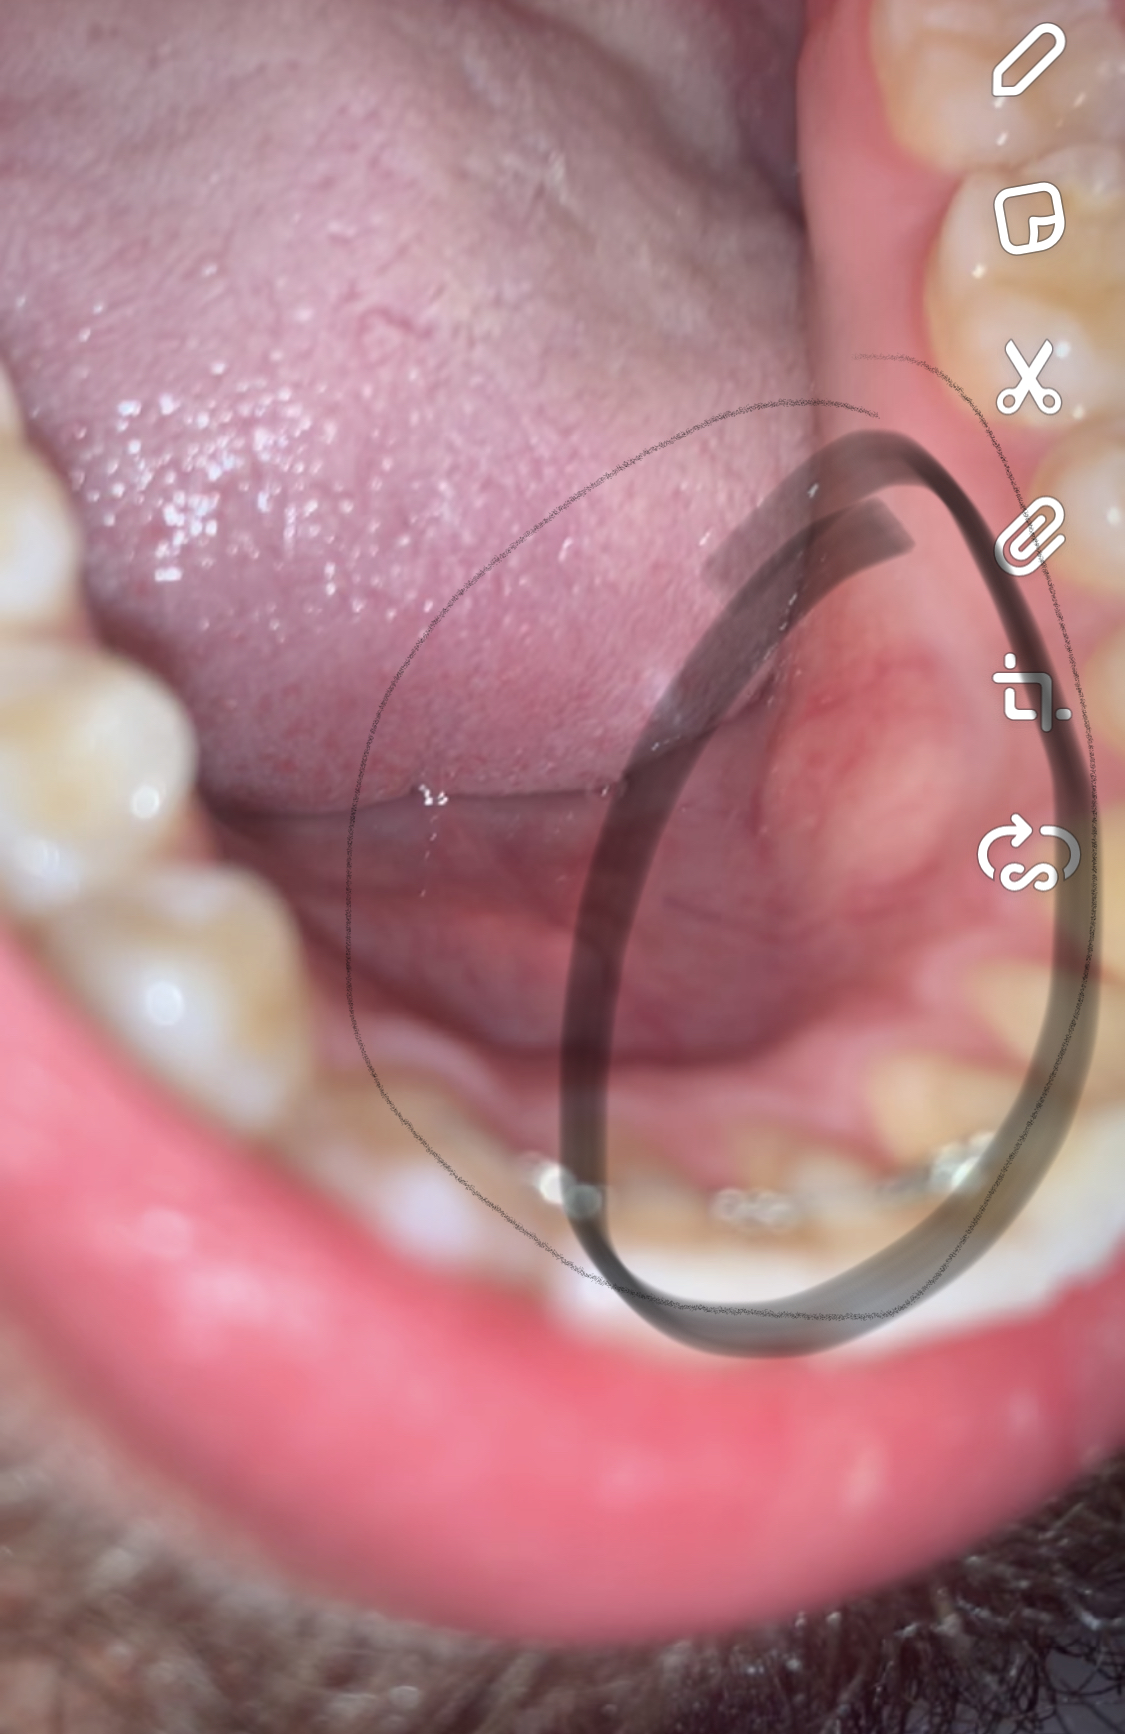

Schmerzen, Schwellung und gar Vereiterung der Gaumen und Rachenmandeln sind die bekannten Anzeichen Das alles kann sich aber weiter ausbreiten, ohne dass einem klar ist, warum die Symptome plötzlich so extrem werden wenn die Zungenmandeln geschwollen sind", erklärt Dr Walter.

Mandel geschwollen einseitig ohne schmerzen. Daher können Betroffene mit vergrößerten Mandeln (auch ohne Mandelentzündung) an z B Schluckbeschwerden, Atemproblemen und Schmerzen im Bereich des Kiefergelenks oder Ohrs leiden Vergrößerte Mandeln sind insbesondere bei Kindern im Alter von 2–6 Jahren relativ weit verbreitet;. Lymphknoten geschwollen sind, ohne dass es Hinweise auf eine Infektion gibt sich die Lymphknotenschwellung nur auf einer Seite befindet (etwa nur in der linken Achselhöhle, nicht aber in der rechten) die tast oder sichtbare Schwellung schon länger (mehr als drei Wochen) und ohne erkennbaren Grund besteht. Mandel und Rachenentzündung Die Tonsillitis bezeichnet eine Entzündung der Mandeln und kann sowohl auf beiden als auch nur auf einer Seite auftreten Die befallenen Mandeln weißen einen weißgelblichen Belag auf und Patienten leiden unter starken Halsschmerzen auch einseitig Die Schmerzen können dabei bis hin zu den Ohren ausstrahlen.

Meine linke Mandel ist seit ca 1 bis zwei Monaten geschwollen, sie tut aber nicht weh Ich weiss nicht mehr woher das kam, evtl nach ner kleinen Grippe (ohne Halsschmerzen) Früher, vor ca 2 Jahren hatte ich die letzte Mandelentzündung, damals auch meist 2mal pro jahr. Bei der eher seltenen Angina PlautVincent ist in der Regel nur eine Gaumenmandel betroffen, die Symptome treten einseitig auf Die Mandel ist entzündlich gerötet, und es bilden sich großflächige schmierige, grauweißliche, stinkende Beläge Es kommt zu Schluckschmerzen und Schwellungen der HalsLymphknoten. Männer und Jungen mit Schwellungen des Hodens sollten den Arzt konsultieren, selbst wenn keine Schmerzen auftreten Hodentumor ist bei jedem Mann oder Jungen eine ernste Angelegenheit, vor allem bei Patienten unter 40 Jahren Die Diagnose kann normalerweise leicht gestellt werden, basierend auf den Symptomen, der körperlichen Untersuchung und.

In manchen Fällen können die Mandeln schmerzfrei anschwellen und nach ein paar en wieder spontan abschwellen, ohne Folgeschäden Aber ebenso können bei dauerhaft geschwollenen Mandeln, im Rahmen einer chronischen Mandelentzündung, Schmerzen ausbleiben. Vergrößerte Mandeln Bei vergrößerten Mandeln handelt es sich um eine vorübergehende oder dauerhafte Schwellung der Gaumenmandeln oder auch der Rachenmandeln Diese kann als Begleitsymptom einer Erkrankung wie beispielsweise eines Infekts auftreten Mit Abklingen dieser schwellen auch die Mandeln wieder ab;. Mein Freund hat seit ein paar en eine Mandelentzündung und da wir zusammen wohnen gehe ich davon aus dass ich mich auch angesteckt habe, meine Mandeln sehen auch geschwollen aus jedoch habe ich keinerlei Schmerzen oder andere Beschwerden sollte ich trotzdem zum Arzt?.

Einseitig geschwollene Mandel seit 2 Wochen?. Thema Schmerzen Schmerzen müssen nicht sein und lassen sich mit einer individuell abgestimmten Schmerztherapie gut in den Griff bekommen Leider geht die Ausheilung nach der OP nicht ganz schmerzfrei über die Bühne – ohne Schmerzmittel wäre ich vermutlich beim Essen an die Decke gegangen. Mandelentzündung ohne Fieber Wenn die Mandeln geschwollen Einseitige Schmerzen und das Gefühl, einen Kloß im Hals zu haben, können zudem auf eine Eiteransammlung an einer der Gaumenmandeln hindeuten, einen sogenannten Peritonsillarabszess.

Ein Arztbesuch ist dann angeraten, wenn man geschwollene Lymphknoten hat, ohne einen Hinweis auf einen Infekt Ebenso, wenn die Lymphknoten nur auf einer Seite geschwollen sind, zum Beispiel nur in der rechten Achselhöhle Hält die zu ertastende oder sichtbare Lymphknotenschwellung über einen Zeitraum von drei Wochen an, ohne dass es einen. Seit einiger Zeit (ich weiß ehrlich gesagt nichtmal ab wann genau) ist meine linke Mandel ziemlich geschwollen Bis jetzt hatte ich damit keine Probleme, war deshalb auch schon etliche Male beim Hausarzt. Halsschmerzen werden häufig durch Viren verursachtEin Querschnitt durch den Rachen zeigt, wie groß der Bereich ist, der erkranken kann – mit und ohne Mandeln Gerade, wenn die Gaumenmandeln operativ entfernt wurden, haben Viren und auch Bakterien „freien Zugang“ zum gesamten Rachenraum, so dass andere Bereiche in Folge einer Erkrankung.